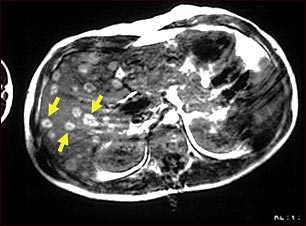

IRM del melanoma del hígado

Esta IRM de la parte superior del abdomen muestra tumores múltiples en el hígado que se han diseminado (metástasis) desde un melanoma maligno en un brazo o pierna. Observe las áreas circulares y claras presentes en todo el hígado (en su mayoría ubicadas del lado izquierdo de la pantalla).